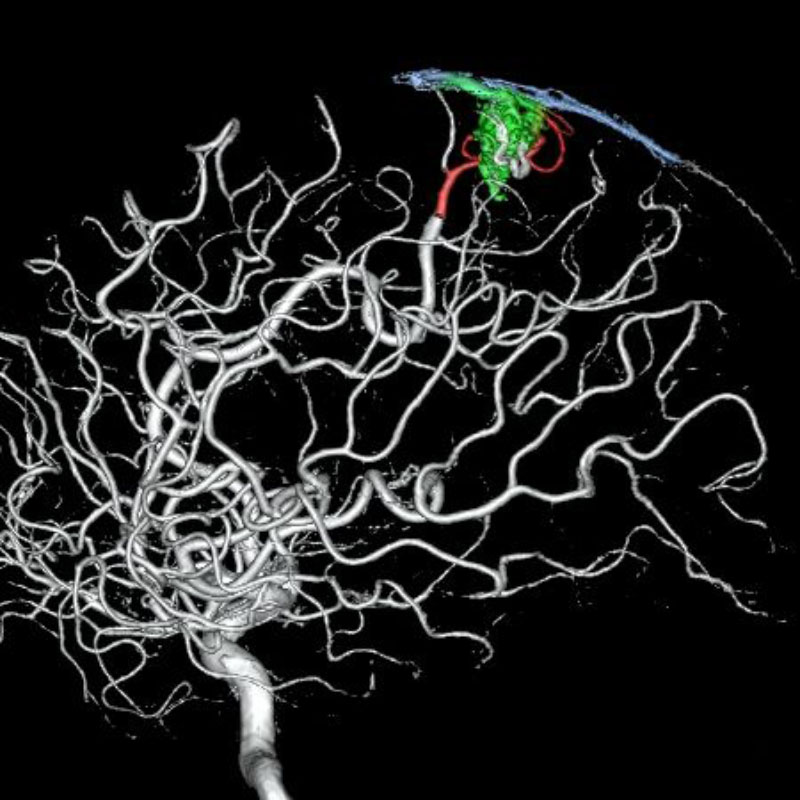

脳動静脈奇形

血管塞栓術

芝野/古谷